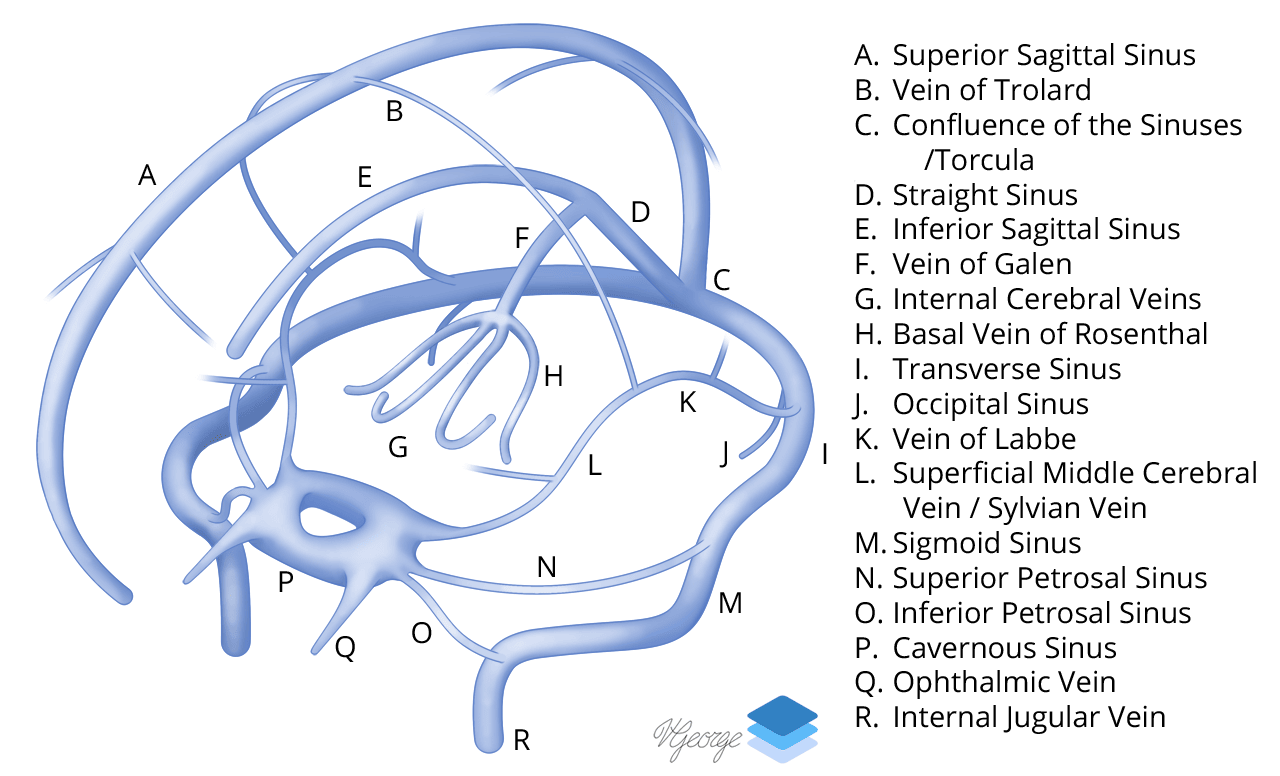

Venous Sinuses.

Approximations of venous vascular territories of the brain.